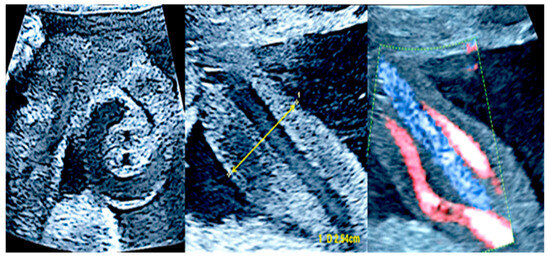

3.4. Single Umbilical Artery